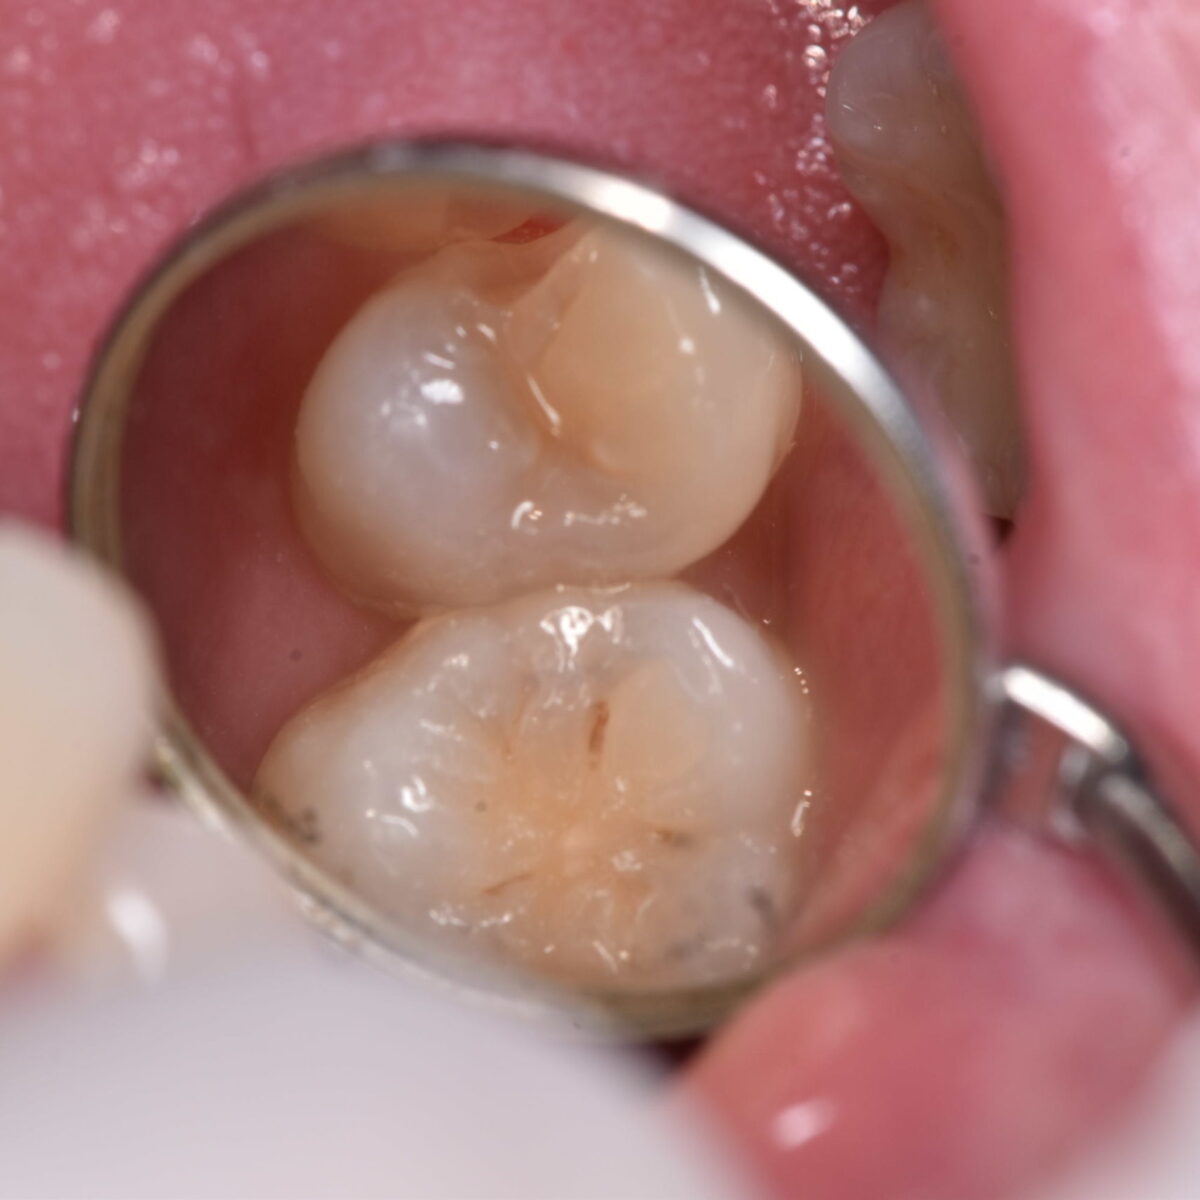

見た目は白くても・・・

【東京メトロ東西線妙典駅 徒歩5分の歯医者】市川、妙典の歯科医院、めぐりデンタルクリニックの梶原です。 今回の話と似たような状況の話は以下に掲載しております 白いつめものの下6 &…